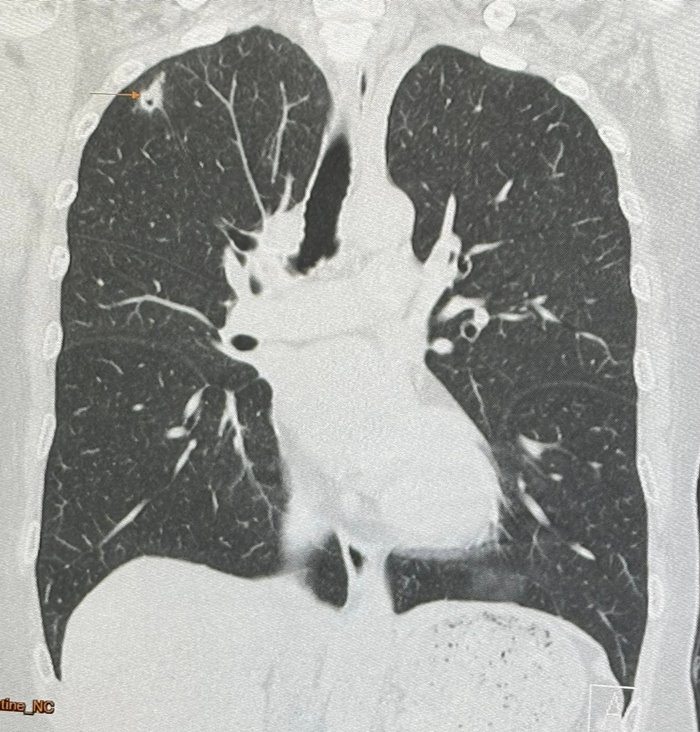

วันที่ 3 มิถุนายน 2567 นพ.มนูญ ลีเชวงวงศ์ แพทย์เฉพาะทางด้านโรคระบบการหายใจ โรงพยาบาลวิชัยยุทธ โพสต์ผ่านเฟซบุ๊ก หมอมนูญ ลีเชวงวงศ์ FC ระบุว่า พบเคสผู้ป่วยหญิงอายุ 52 ปี บ้านอยู่ กทม. ปกติแข็งแรงดี ไม่ไอ ไม่มีไข้ ไม่เบื่ออาหาร น้ำหนักไม่ลด ไม่ปวดหัว ไม่เคยสูบบุหรี่ ไม่มีโรคประจำตัว ไปตรวจร่างกายประจำปี เมื่อ 12 พฤษภาคม ที่ผ่านมา เอกซเรย์ปอดพบก้อนเล็ก ๆ เกิดขึ้นใหม่ที่ปอดขวากลีบบน

เอกซเรย์ปอดก่อนหน้านั้น 1 ปีปกติ ทำคอมพิวเตอร์ปอดพบก้อนขนาด 0.9 × 0.9 × 1.7 เซนติเมตร เห็นโพรงอยู่ข้างในก้อนที่ปอดขวากลีบบน ตรวจเลือดไม่ติดเชื้อเอชไอวี